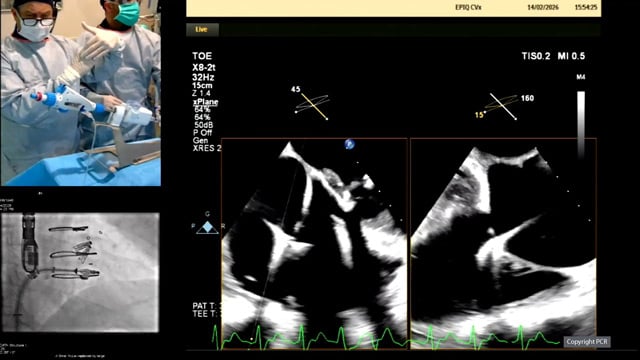

Tricuspid: LIVE Educational Case from The Prince Charles Hospital, Metro North Health - Brisbane, Australia

14 Feb 2026 – From PCR Tokyo Valves 2026

This educational session from The Prince Charles Hospital in Brisbane offers a comprehensive live case demonstration of tricuspid TEER. It covers patient selection, procedural planning with multimodality imaging, step-by-step procedural strategies, and post-procedural assessment emphasizing echocardiographic evaluation and short-term outcomes.